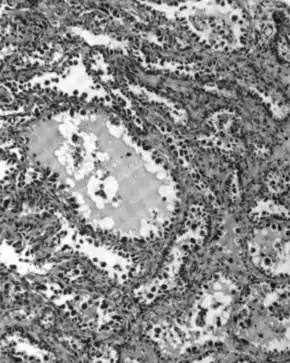

Micrograph of serous carcinoma, a type of ovarian cancer, diagnosed in peritoneal fluid

Serous carcinoma

Serous carcinoma of ovary

Serous ovarian cancer is the most common type of epithelial ovarian cancer and it accounts for about two-thirds of cases of epithelial ovarian cancer.[28] Low-grade serous carcinoma is less aggressive than high-grade serous carcinomas, though it does not typically respond well to chemotherapy or hormonal treatments.[28] Serous carcinomas are thought to begin in the Fallopian tube.[68][69] High grade serous carcinoma accounts for 75% of all epithelial ovarian cancer.[67] About 15–20% of high grade serous carcinoma have germline BRCA1 and BRCA2 mutations.[67] Histologically, the growth pattern of high grade serous carcinoma is heterogenous and has some papillary or solid growth patterns.[67] The tumor cells are atypical with large, irregular nuclei.[67] It has a high proliferation rate.[67] 50% of the time, serous carcinomas are bilateral, and in 85% of cases, they have spread beyond the ovary at the time of diagnosis.[70]